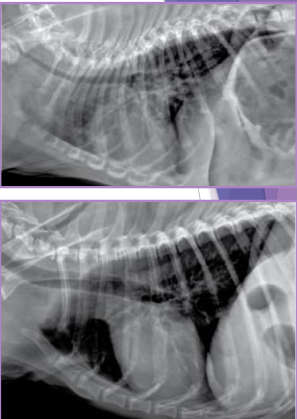

Diaphragmatic Hernia

Et: trauma, pressure gradient disruption, genetic

abdominal organs migrate into thorax, liver is #1

Peritoneopericardial d. hernia (PPDH) → congenital

Sig: Cocker spaniel, Weimaraner, Himalayan, DLH

Cs: shock(acute), dyspnea(chronic), exercise intolerance, ADR

Congenital is asymptomatic

Tears → weakest areas: muscle

Dt: thoracic rads (#1), US, CT

Tx: Sx (8-16w if congenital) (trauma: be ready for anything)

abdominal explore, identify hernia, reduce contents, close defect (absorbable 3-0 PDS, simple continuous, dorsal → ventral), remove air

Caution of adhesions

Do not close the pericardial sac (genetic)

Risk: re-expansion pulmonary edema, abdominal compartment syndrome, ARDS

Do NOT manually re-expand lungs, do not close pericardial sac